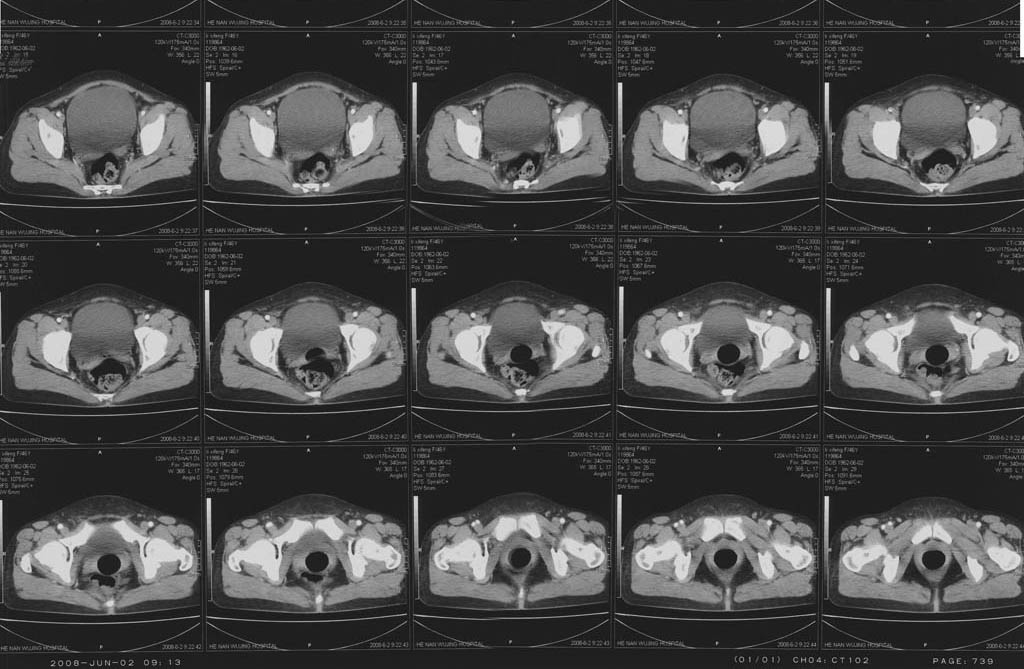

5年前子宫肌瘤 子宫切除,2年前整个下腹痛2周余病因不名,2008年5月底再次左下腹痛行ct,6月2日ct增强,请指教

后面的图像就是增强的啊,包块下部还有细小的钙化点